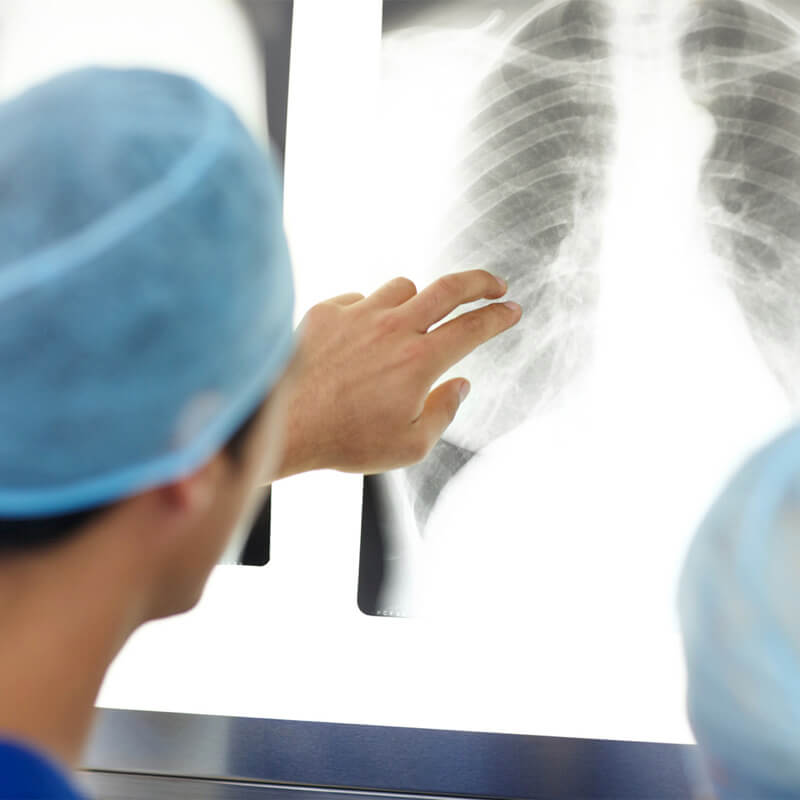

WHICH BODY PARTS CAN VAPING HARM?

The more studies are done, the more dangers are exposed. to see the vital organ damage connected to vaping.